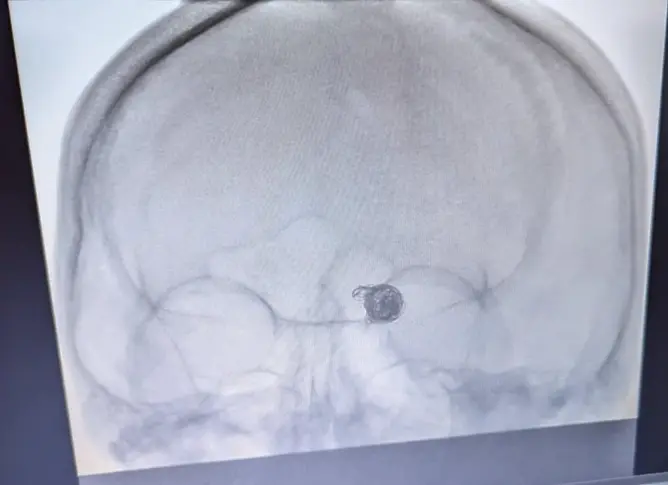

Първата ендовазална емболизация на мозъчно-съдова аневризма успешно извършена в УМБАЛ „Д-р Георги Странски“

За първи път в историята на Университетската многопрофилна болница за интензивно лекуване „ Д-р Георги Странски “- Плевен, в Клиниката по неврохирургия с началник доцент доктор Илия Вълков, беше осъществена сполучлива ендовазална емболизация на мозъчно-съдова аневризма (артерия базиларис).

По време на комплицираната процедура, екипът от висококвалифицирани лекари на Клиниката по неврохирургия употребява най-съвременна технология и инсталация на международно равнище. Тази намеса е скъпоструваща и не се прави във всички здравни заведения, само че с помощта на напъните на медицинския личен състав и съществуването на съвременна техника, тя към този момент е допустима и в УМБАЛ „ Д-р Георги Странски “.